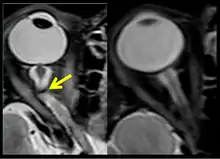

On 2 November 2017, scientists reported that significant changes in the position and structure of the brain have been found in astronauts who have taken trips in space, based on magnetic resonance imaging (MRI) studies. Astronauts who took longer space trips were associated with greater brain changes.[11][12]

Intracranial pressure (ICP) needs to be directly measured before and after long duration flights to determine if microgravity causes the increased ICP. On the ground, lumbar puncture is the standard method of measuring cerebral spinal fluid pressure and ICP,[6][44] but this carries additional risk in-flight.[4] NASA is determining how to correlate ground-based MRI with inflight ultrasound[4] and other methods of measuring ICP in space is currently being investigated.[44]

The third case of visual changes while on board the ISS had no changes in visual acuity and no complaints of headaches, transient visual obscurations, diplopia or pulsatile tinnitus during the mission. Upon return to Earth, no eye issues were reported by the astronaut at landing. Fundus examination revealed bilateral, asymmetrical disc edema. There was no evidence of choroidal folds or cotton-wool spots, but a small hemorrhage was observed below the optic dics in the right eye. This astronaut had the most pronounced optic-disc edema of all astronauts reported to date, but had no choroidal folds, globe flattening or hyperopic shift. At 10 days post landing, an MRI of the brain and eyes was normal, but there appeared to be a mild increase in CSF signal around the right optic nerve.[5]

The sixth case of visual changes of an ISS astronaut was reported after return to Earth from a 6-month mission. When he noticed that his far vision was clearer through his reading glasses. A fundus examination performed 3 weeks postflight documented a grade 1 nasal optic-disc edema in the right eye only. There was no evidence of disc edema in the left eye or choroidal folds in either eye (Figure 13). MRI of the brain and eyes days postflight revealed bilateral flattening of the posterior globe, right greater than left, and a mildly distended right optic nerve sheath. There was also evidence of optic-disc edema in the right eye. A fundus examination postflight revealed a "new onset" cotton-wool spot in the left eye. This was not observed in the fundus photographs taken 3 weeks postflight.[5]